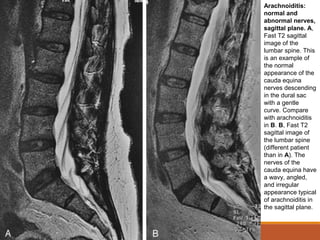

Alterações Inflamatórias

Aracnoidite:

◦Na RM, os achados são mais bem visualizados em T2:

◦ As raízes nervosas podem estar unidas ao invés de igualmente distribuídas

através do saco tecal.

◦ Nervos podem ficar aderidos à dura-máter de modo que pareça que o saco

tecal esteja vazio, sem raízes nervosas presentes.

◦ Nas imagens sagitais, os nervos da cauda eqüina podem ter uma aparência

irregular, angulada ou ondulada, em lugar da curva descendente suave

normal.

Arachnoiditis:

normal and

abnormal nerves,

sagittal plane. A,

Fast T2 sagittal

image of the

lumbar spine. This

is an example of

the normal

appearance of the

cauda equina

nerves descending

in the dural sac

with a gentle

curve. Compare

with arachnoiditis

in B. B, Fast T2

sagittal image of

the lumbar spine

(different patient

than in A). The

nerves of the

cauda equina have

a wavy, angled,

and irregular

appearance typical

of arachnoiditis in

the sagittal plane.